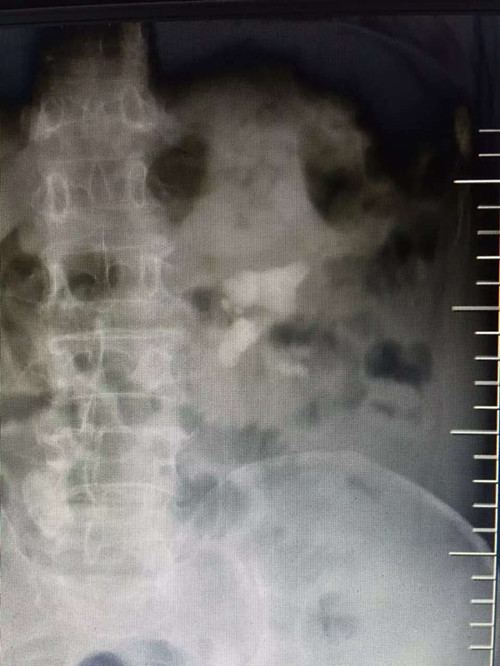

泌尿外科手术效果图